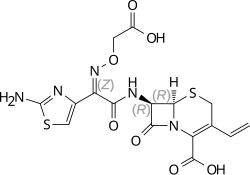

| Formula | C16H15N5O7S2 |

| Molar mass | 453.44 g·mol−1 |

| 3D model (JSmol) | |

| |

| |

| | |

The bactericidal action of Cefixime is due to the inhibition of cell wall synthesis. It binds to one of the penicillin binding proteins (PBPs) which inhibits the final transpeptidation step of the peptidoglycan synthesis in the bacterial cell wall, thus inhibiting biosynthesis and arresting cell wall assembly resulting in bacterial cell death.